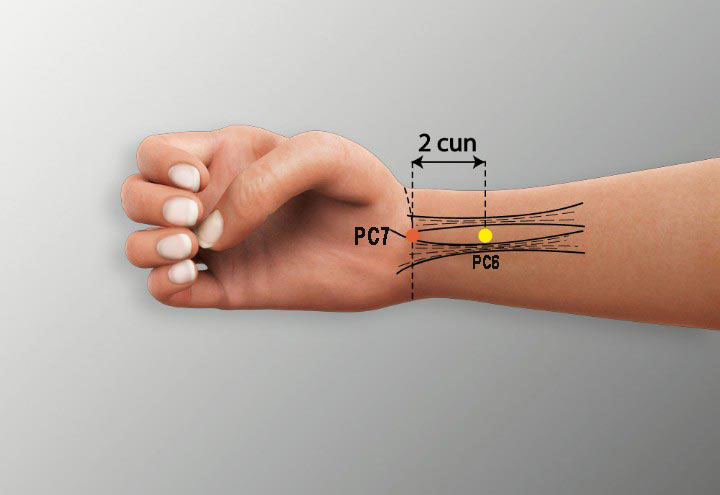

5. Carpal Tunnel Syndrome

Repetitive strain in the wrist causes numbness and pain. Common acupoints include:

- PC6 (Neiguan): On the inner forearm, above the wrist. Relieves wrist pain and numbness.

- PC7 (Daling): At the wrist crease, center of the palm side. Reduces carpal tunnel symptoms.

- LI4 (Hegu): Promotes pain relief and circulation.

- LU9 (Taiyuan): On the wrist, near the radial artery. Supports wrist strength and reduces swelling.

- AshI Points: Tender points around the wrist for localized relief.

Protocol: Acupuncture is applied weekly for 6-10 weeks, often with wrist splints for support.